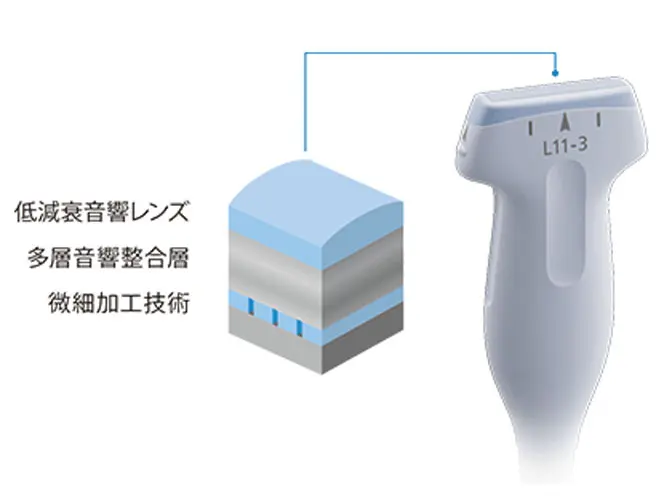

・シンプルな操作性と高画質を両立

高感度広帯域プローブ(L11-3)

浅部の描出改善と深部の視認性を両立。

プレミアムクラスに迫る画質を実現。